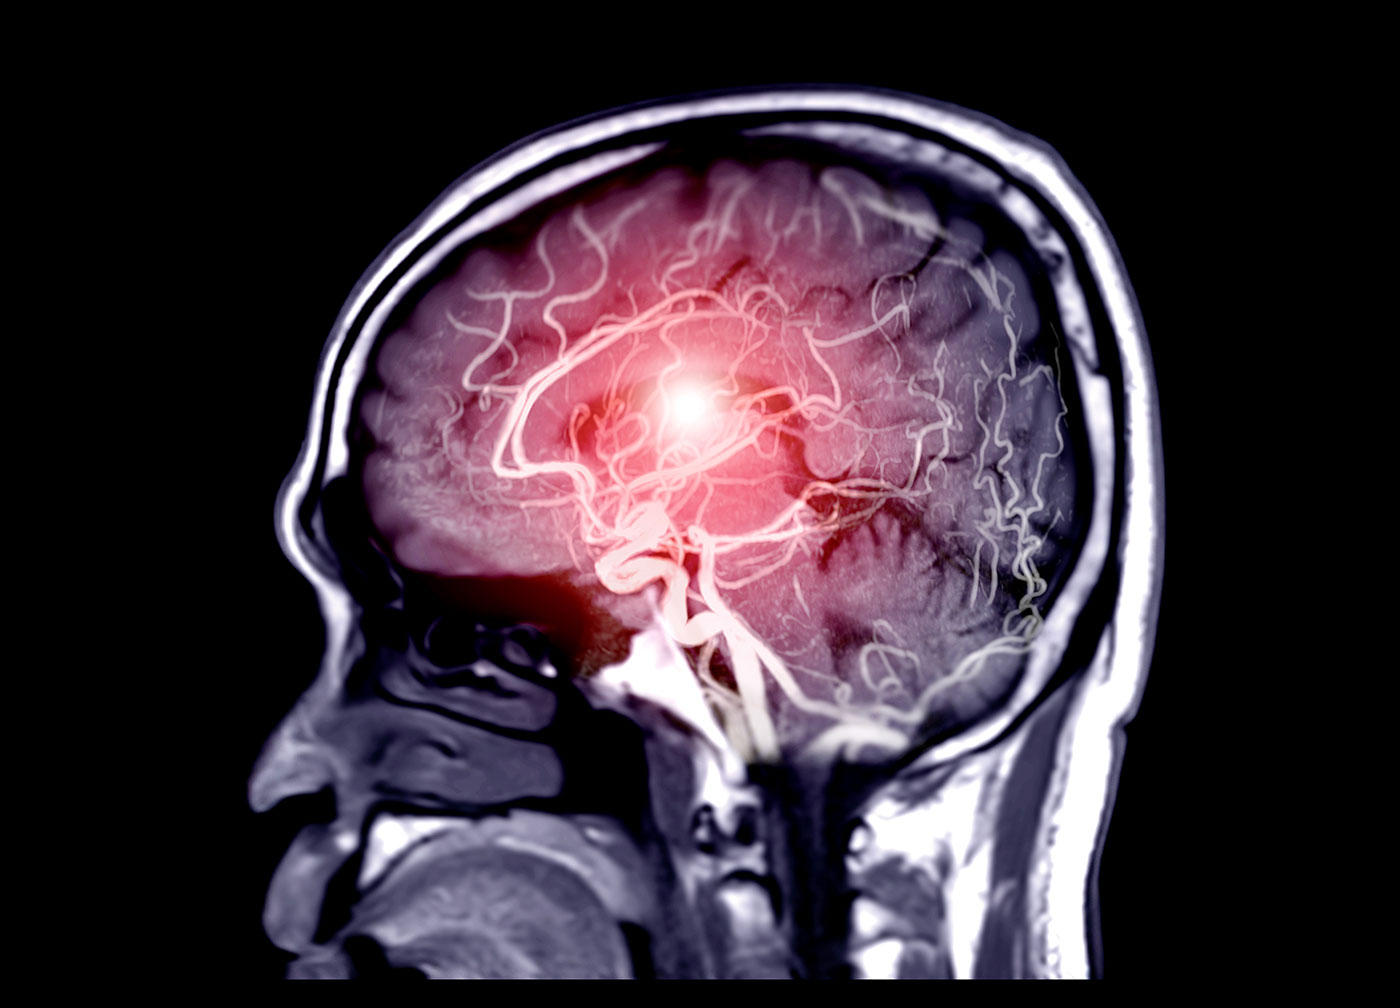

Una novedosa malla para tratar los aneurismas dentro del cerebro

Un implante trenzado podría proporcionar una opción de tratamiento eficaz y mínimamente invasiva para los aneurismas intracraneales bifurcados, potencialmente mortales.

Concretamente, el Sistema Neurovascular Contour de Cerus Endovascular (Oxford, Reino Unido) está compuesto por un implante trenzado de malla fina preformada con propiedades de memoria de forma y un sistema de colocación de microcatéter. Este dispositivo combina un desviador y un interruptor de flujo para apuntar al cuello de un aneurisma intracraneal, lejos de la cúpula vulnerable.

Asimismo, el perfil de seguridad mejorado permite su uso para tratar una variedad de morfologías y tamaños de aneurismas, incluidas las bifurcaciones de cuello ancho no rotas.